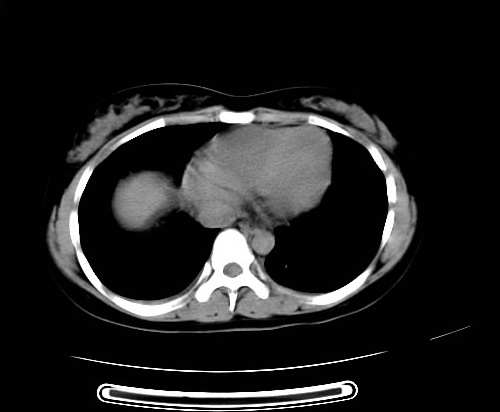

女 16岁  右上腹痛一天,无其他不适

肿块最大径位于十二指肠降段与水平段移行处,并且与肝脏压迹呈“0”形征,可以考虑位于肝外并与胃肠道关系紧密,考虑胃肠道间质瘤(gist)可能较大,须除外神经节起源肿瘤。

肿块与十二指肠关系密切,支持间质瘤诊断.肝脏与结肠均为受压改变.

我坚决反对您的观点,该病例定位:横结肠肝曲与升结肠之间的肠系膜及部分肠壁。请看下图:

病灶巨大,少部分向肠腔内生长,大部分向长腔外生长。其密度不均匀,增强显示明显不均匀强化,并见有大片状始终不强化的不规则坏死液化区。虽然病灶中上部形态尚可,病人又如此年轻,但中下部形态、密度、强化特点强烈提示为恶性病灶。综上,我考虑本病例为:恶性胃肠道间质瘤。